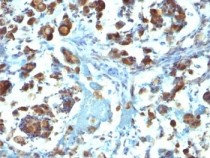

Immunohistochemistry: Formalin-fixed, paraffin-embedded Human colon carcinoma stained with ARG56057 anti-MUC3 antibody [M3.1].

ARG56057 anti-MUC3 antibody [M3.1] IHC-P image

Immunohistochemistry: Formalin-fixed, paraffin-embedded Human gastric carcinoma stained with ARG56057 anti-MUC3 antibody [M3.1].